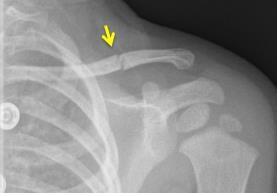

Your child has a fractured collarbone (clavicle). This fracture is treated with a sling.

A fractured collarbone is a common injury in children. The fracture is treated with a sling. If your child is young and won’t wear the sling, this is not a problem. Collarbone fractures almost always heal without any problems or complications.